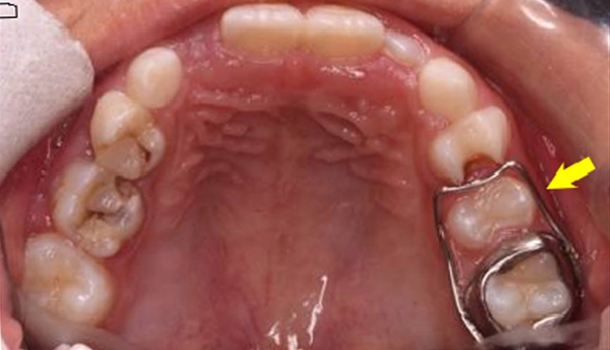

儿童乳牙缺失,需要佩戴间隙保持器吗?...